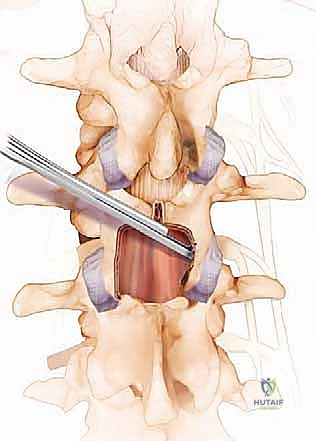

خطوة بخطوة: كيف تتم جراحة تخفيف الضغط المجهرية مع د. محمد هطيف؟

لفهم مدى دقة وأمان هذه الإجراءات الحديثة، نستعرض معكم الخطوات الأساسية لعملية تخفيف الضغط المجهرية التي يجريها فريق الأستاذ الدكتور محمد هطيف في أحدث مستشفيات صنعاء:

1. التجهيز والتخدير: يتم إخضاع المريض للتخدير العام لضمان عدم الشعور بأي ألم. يتم وضع المريض على بطنه على طاولة عمليات خاصة مصممة لتقليل الضغط على البطن وفتح المسافات بين الفقرات.

2. الشق الجراحي الدقيق: باستخدام الإرشاد بالأشعة السينية داخل غرفة العمليات (C-arm)، يتم تحديد المستوى الدقيق للفقرات المصابة. يقوم الدكتور هطيف بعمل شق جراحي صغير (غالباً بضعة سنتيمترات) في منتصف الظهر.

3. التشريح العضلي اللطيف: بدلاً من قطع العضلات، يتم إبعاد العضلات المحيطة بالعمود الفقري بلطف شديد باستخدام مبعدات خاصة للوصول إلى العظام، مما يقلل الألم بعد العملية ويسرع الشفاء.

4. استخدام الميكروسكوب الجراحي: هنا تبرز خبرة الدكتور هطيف. يتم إدخال الميكروسكوب الجراحي عالي التكبير والإضاءة لتكبير مجال الرؤية بشكل هائل.

5. تخفيف الضغط (Decompression): باستخدام أدوات مجهرية دقيقة وحفارات عالية السرعة (High-speed burrs)، يتم إزالة النتوءات العظمية، وجزء من الصفيحة الفقرية، والرباط الأصفر المتضخم. يتم ذلك بحذر شديد مليمتر بمليمتر حتى يتم تحرير كيس الجافية (الذي يحوي الأعصاب) وجذور الأعصاب بالكامل.

6. التأكد من التحرير: يقوم الجراح بالتحقق من أن الأعصاب أصبحت حرة تماماً ولا يوجد أي ضغط متبقي في القناة المركزية أو الثقوب الجانبية.

7. الإغلاق التجميلي: يتم إزالة المبعدات لتعود العضلات إلى مكانها الطبيعي. تُغلق الطبقات العميقة والجلد بغرز تجميلية دقيقة لا تترك أثراً كبيراً.

خطوات جراحة تخفيف الضغط على الأعصاب الشوكية